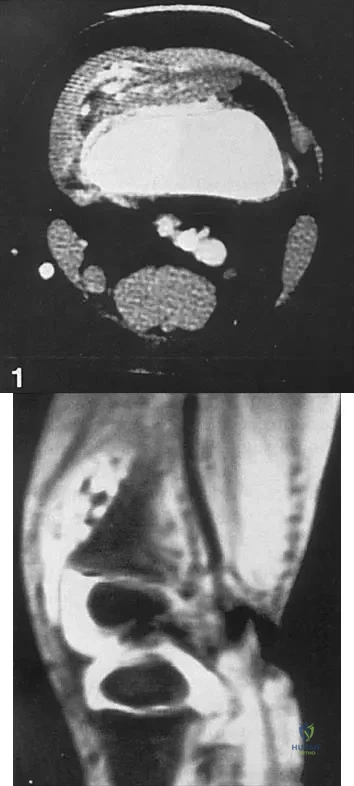

The condition shown in Figures 9a and 9b is most likely the result of

Explanation